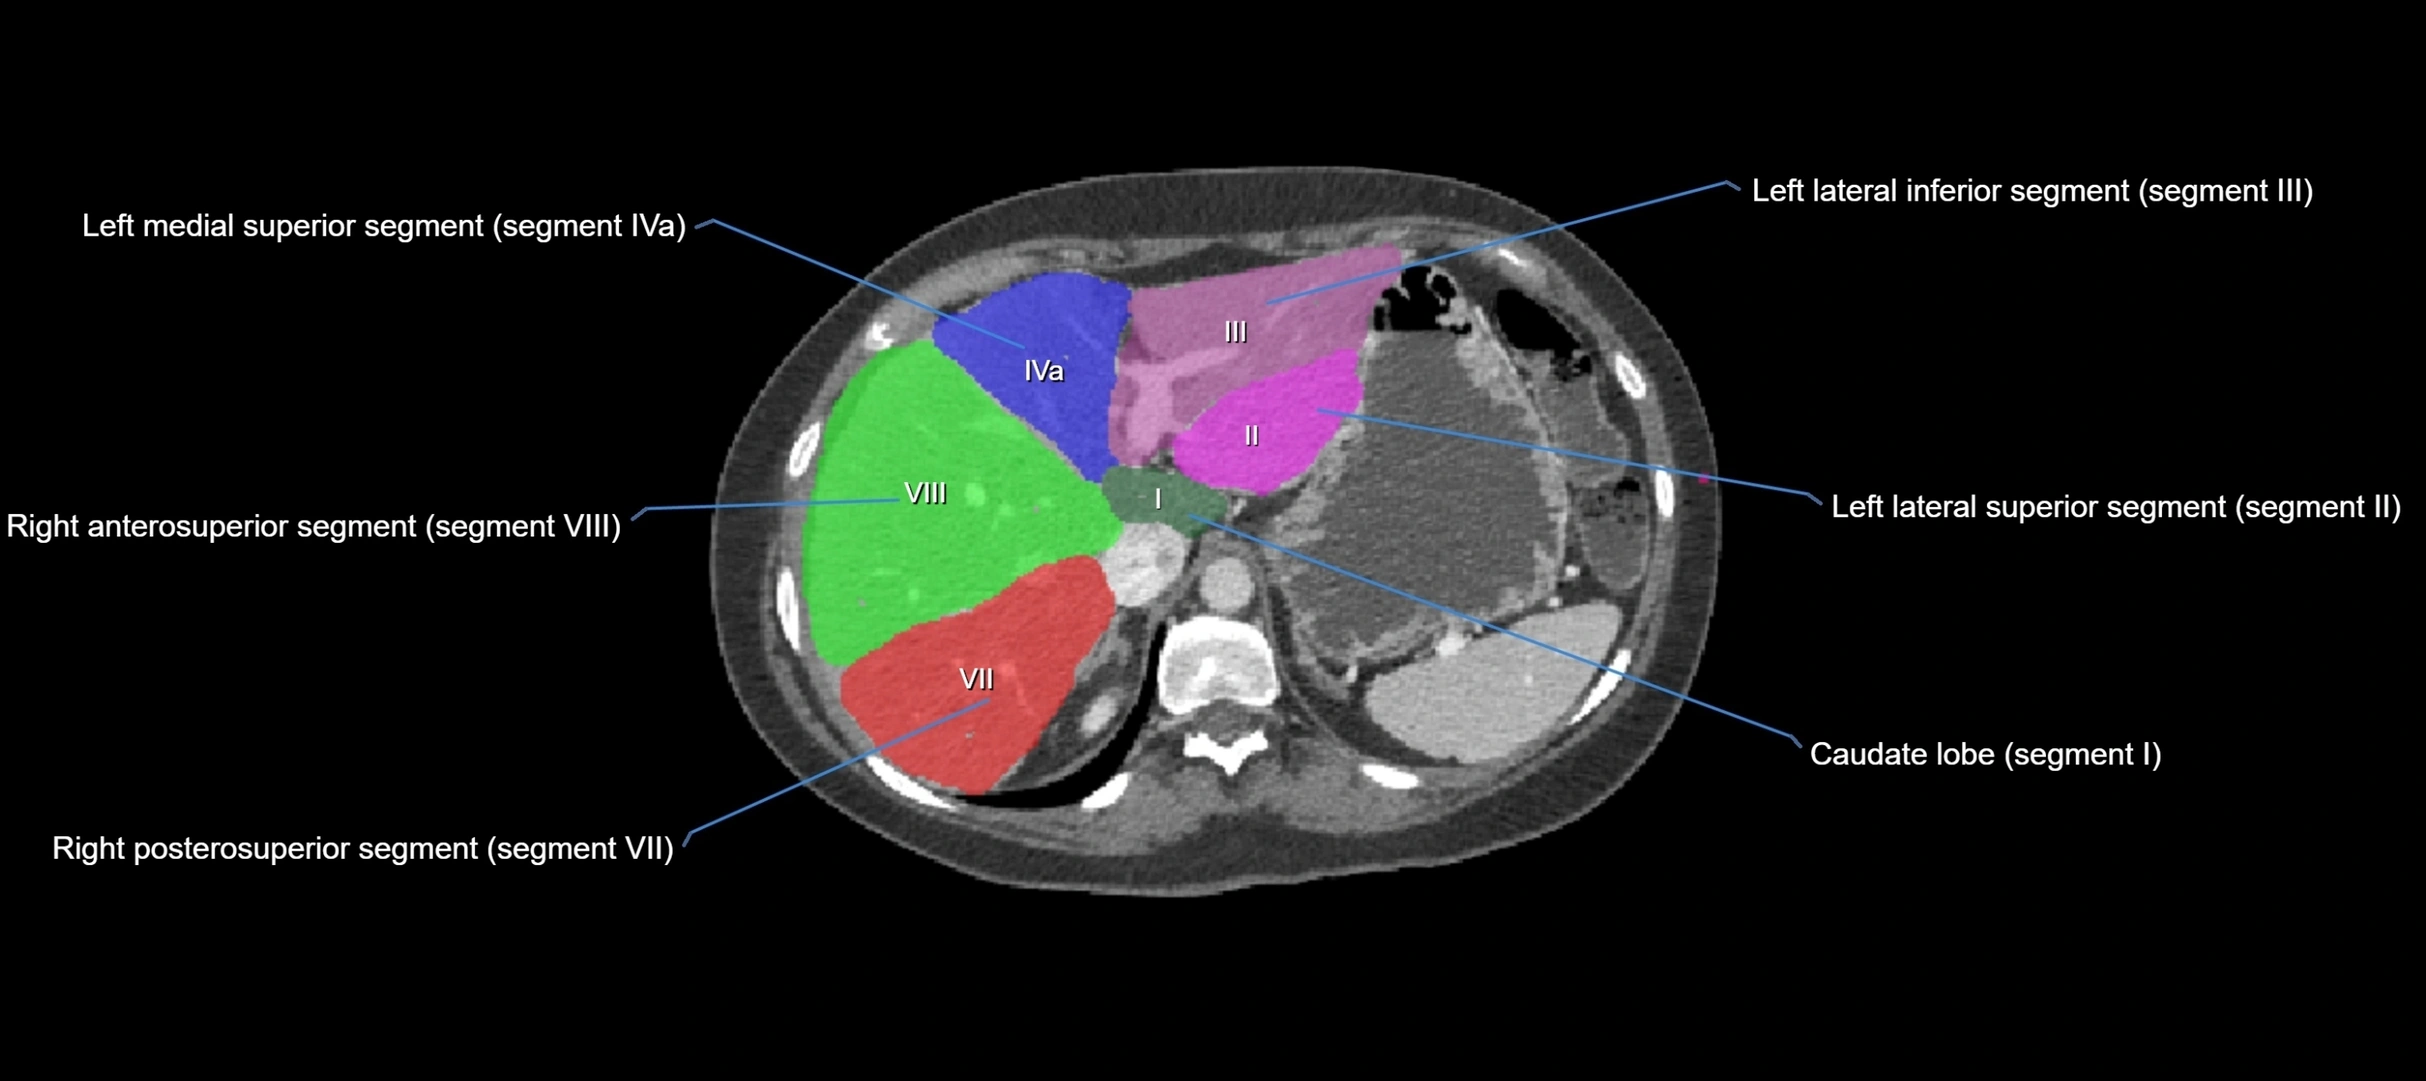

CT Appearance

CT Pre-Contrast:

• Caudate lobe appears as a soft-tissue density, isodense to the rest of the liver

• Enlargement may be appreciated in cirrhosis or Budd–Chiari syndrome

CT Post-Contrast:

• Homogeneous enhancement in the portal venous phase, similar to rest of liver

• Independent venous drainage into the IVC may be visualized

• Lesions follow characteristic CT enhancement patterns (HCC: arterial hyperenhancement with washout; hemangiomas: peripheral nodular enhancement with centripetal fill-in)

CT Venous Phase (functional significance):

• Caudate lobe often enhances relatively more than other lobes in Budd–Chiari syndrome, due to preserved venous outflow

CT Image

image